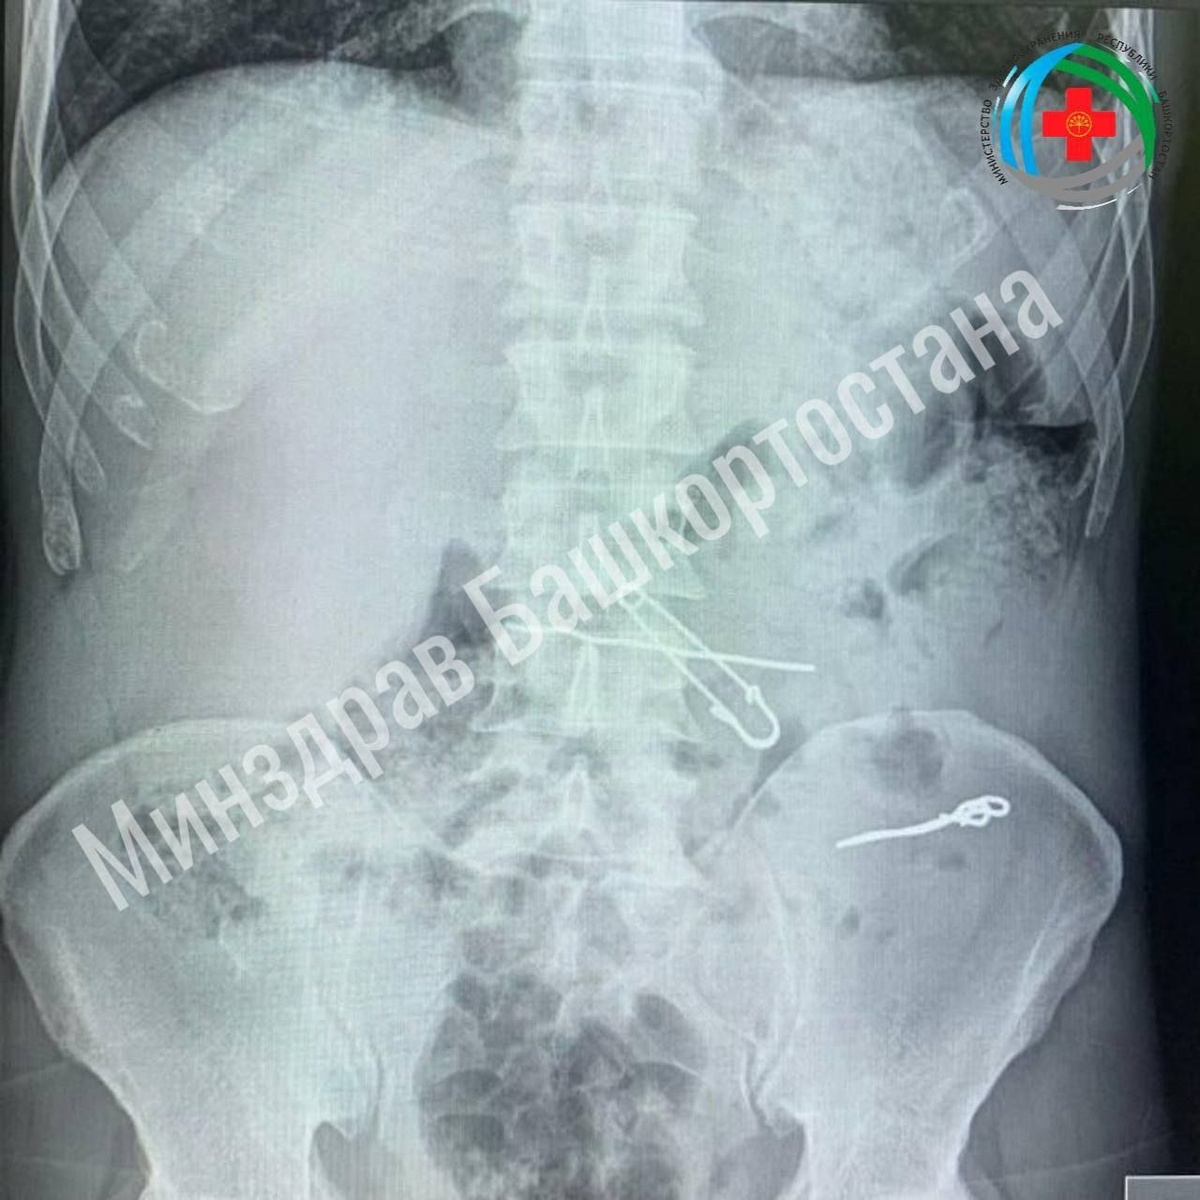

#Как_много_вопросов_как_мало_ответов🤦‍♀️ В больнице скорой медицинской помощи республики произошло необычное происшествие: пациент проглотил ключи, скрепки, булавку и проволоку. История началась с того, что мужчина обратился в приёмный покой с жалобами на боли в животе. После проведённых обследований в его толстой кишке были обнаружены проволоки и скрепки различной длины: 47, 62 и 90 мм. Кроме того, в желудке были обнаружены булавка и проволока. Пациента госпитализировали в отделение гнойной хирургии. В ходе операции хирурги успешно удалили все инородные тела.

В больнице скорой медицинской помощи республики произошло необычное происшествие: пациент проглотил ключи, скрепки, булавку и проволоку.

История началась с того, что мужчина обратился в приёмный покой с жалобами на боли в животе. После проведённых обследований в его толстой кишке были обнаружены проволоки и скрепки различной длины: 47, 62 и 90 мм. Кроме того, в желудке были обнаружены булавка и проволока. Пациента госпитализировали в отделение гнойной хирургии.

В ходе операции хирурги успешно удалили все инородные тела.